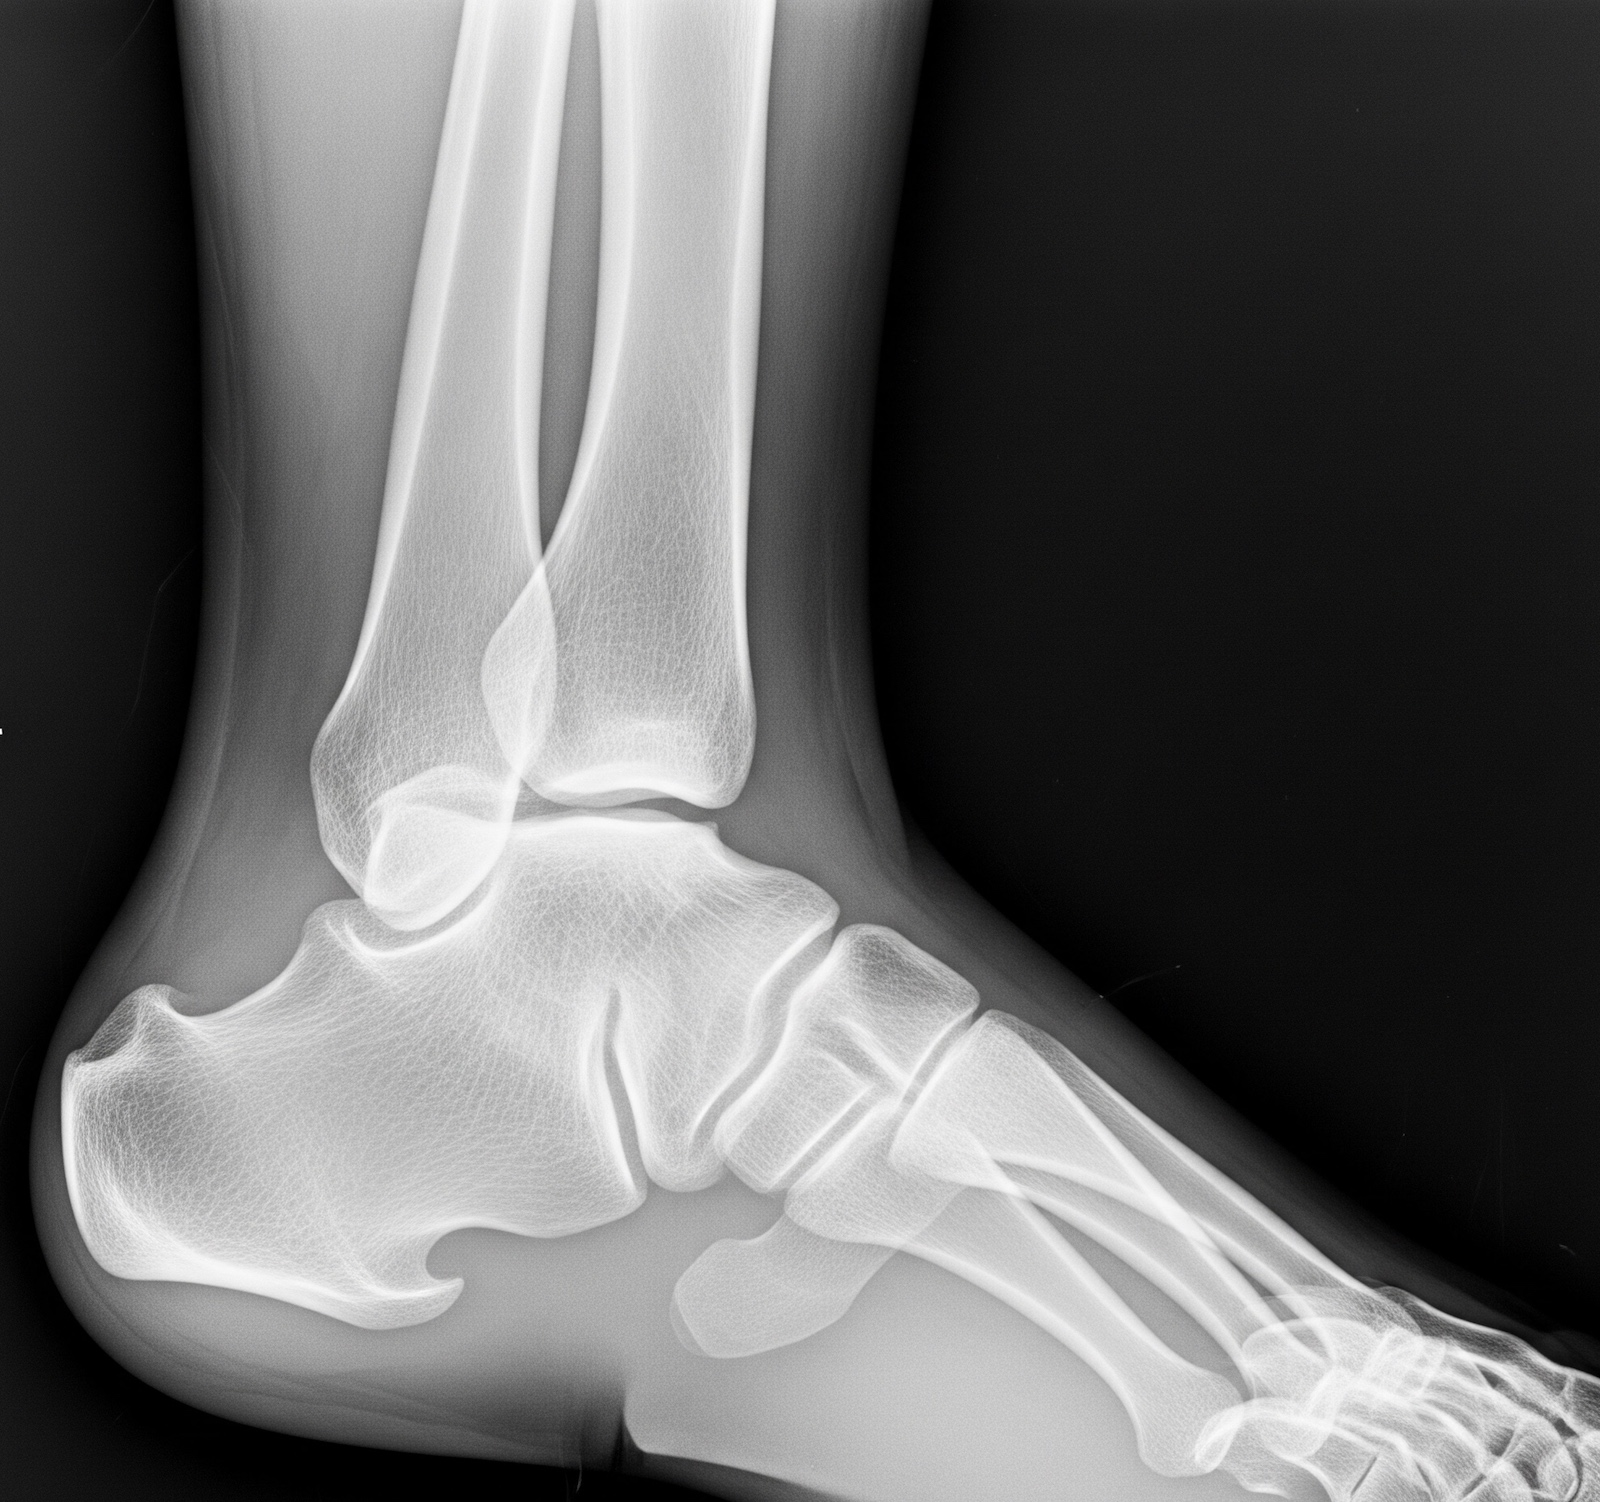

Оценка эффекта проводимого консервативного лечения, возможности проведения органосохраняющего оперативного вмешательства, а также подготовка и планирование этапа эндопротезирования проводились с использованием:

- Рентгенография дистальной части голени с захватом зоны голеностопного сустава и стопы в двух проекциях (рис. 1).